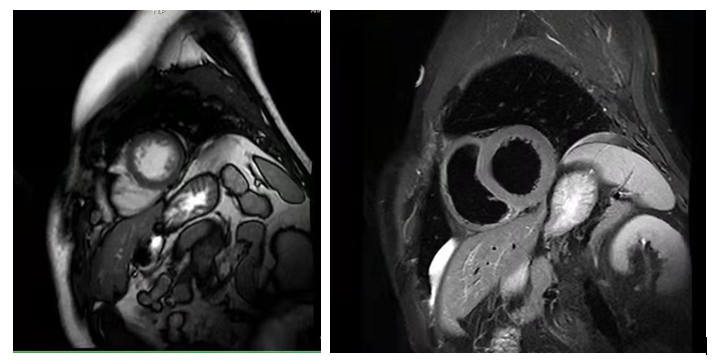

心脏MRI图像示例:

图3. 左室短轴位亮血与黑血序列(左图亮血、右图黑血),垂直于左室长轴的层面,主要显示左心室各壁